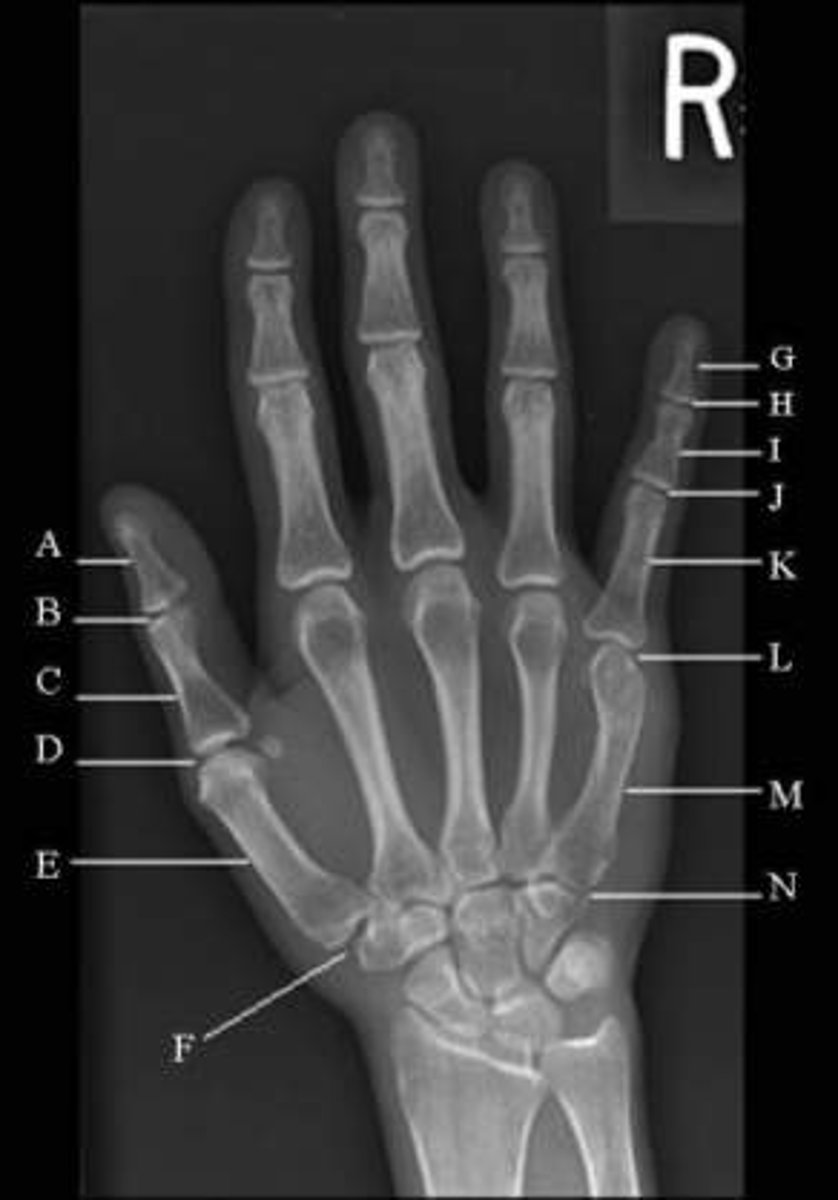

The two portions of the thumb are

proximal phalanx and distal phalanx

The three portions of each finger are the

proximal phalanx, middle phalanx, and distal phalanx

the three parts of each phalanx, starting distally, are the

Head, body/shaft, base

list three parts of each metacarpal, starting proximally

base, body/shaft, head

The name of the joint between the proximal and distal phalanges of the first digit is the`

interphalagial joint